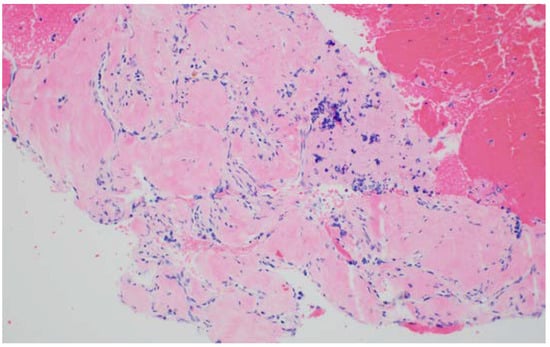

4. EUS-Fluid Acquisition

5. EUS-Tissue Acquisition

5.1. EUS-Fine Needle Aspiration (FNA)